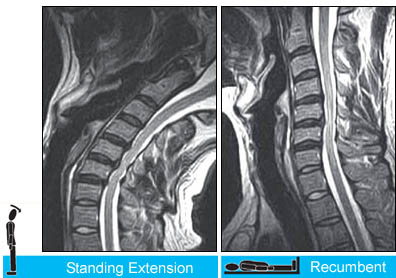

Case #3:Upright Dynamic MRI Reveals Hidden Disc Herniation

You need the upright scan to see the position-dependent focal posterior disc herniation at the C4/5 level (arrow). Note the asscociated spinal cord compression on the standing-extension scans in both the sagittal (top left) and axial planes(bottom left).

(Images courtesy of Melville MRI, P.C.)